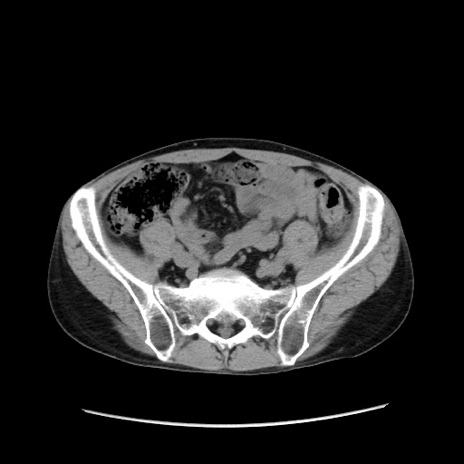

冠状断像

【症例】40歳代 男性

【主訴】腹痛

【現病歴】4時間ほど前に電車に乗車中に臍部上より腹痛出現。徐々に増悪し起立困難となり、救急外来受診。生ものは数日食べていない。今朝お雑煮を食べた。

【身体所見】BT 36.8℃、BP 117/84mmHg、HR 91/min、SpO2 97%、苦悶様、腹部:臍上部広範囲圧痛あり、反跳痛±

【データ】WBC 8100、CRP 0.03